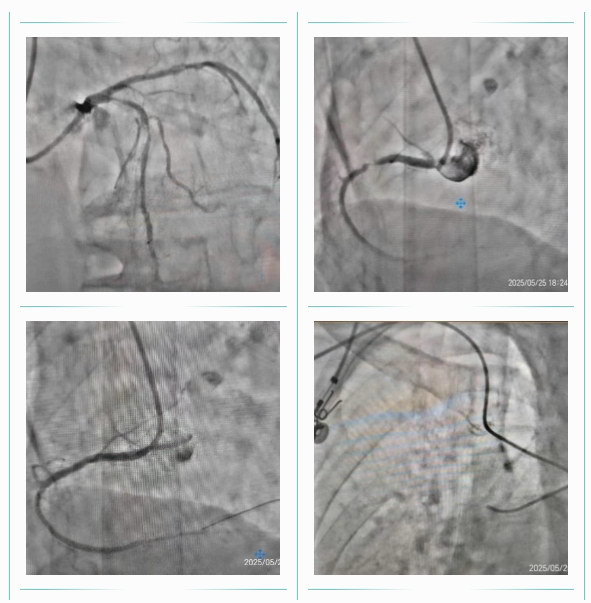

手术过程由谭院长指导,心血管内二科主任马斌亲自操作。由于患者年事已高,上肢入路血管硬化和迂曲,手术难度极大。但在精湛的技术操作下,冠脉造影手术依然顺利完成。造影结果显示,患者左前降支口部至中段有两处90%的狭窄,右冠状动脉近段也有90%的狭窄。在向家属详细说明了相关风险后,患者及其家属立即同意进行支架植入手术。经过约40分钟的手术,成功在患者右冠状动脉植入了一枚支架,术中未出现任何心脏不适症状,患者及其家属对谭院长和马斌主任表达了真挚的感谢。